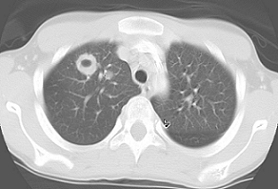

Due to the characteristic cavitary lesion on chest radiographs, suspicion for Staphylococcus aureus pneumonia was high; hence, treatment with an intravenous (IV) vancomycin and IV cephalosporin was initiated. Several days of antimicrobial therapy resulted in no clinical improvement. A computed tomography (CT) scan of the thorax showed a large cavitary air-space opacity in the right lung and perihilar region, areas of necrosis and cavitation, and dense consolidation in right lower lung.

Figures 2a and 2b. Thoracic CT scans showed a large air-space opacity and areas of necrosis and consolidation.